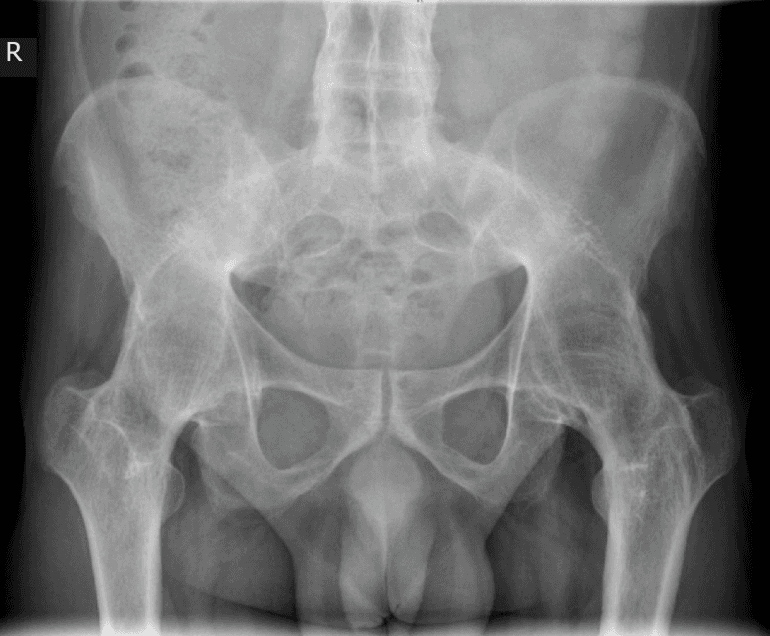

when person needs hip replacement surgery ? Why Hip Joint Replacement?

The hip joint is an important part of our body’s mobility system, allowing us to walk, sit, and perform daily activities with ease. Hip pain can deeply impact the quality of life.

Are you someone who is unable to sleep well because of hip pain? Do you find it difficult to do simple everyday tasks like bending forward, walking, climbing stairs, riding a bike, or driving a car ? Is the pain impeding you from doing your favourite outdoor activities? A large number of people experience hip pain due to various underlying conditions, like

• Avascular necrosis of hip joint (Osteonecrosis of femoral head)

• Ankylosing Spondylitis

• Post traumatic hip arthritis (secondary to acetabulum fracture or failed neck femur fracture)

• Primary Hip Osteoarthritis can lead to chronic pain and reduced mobility. When conservative treatments such as medications, physical therapy, and lifestyle changes are no longer effective,it is high time you meet the right doctor for correct diagnosis & treatment. Modern hip replacement surgery helps millions of patients to get relief from hip pain and gain mobility..